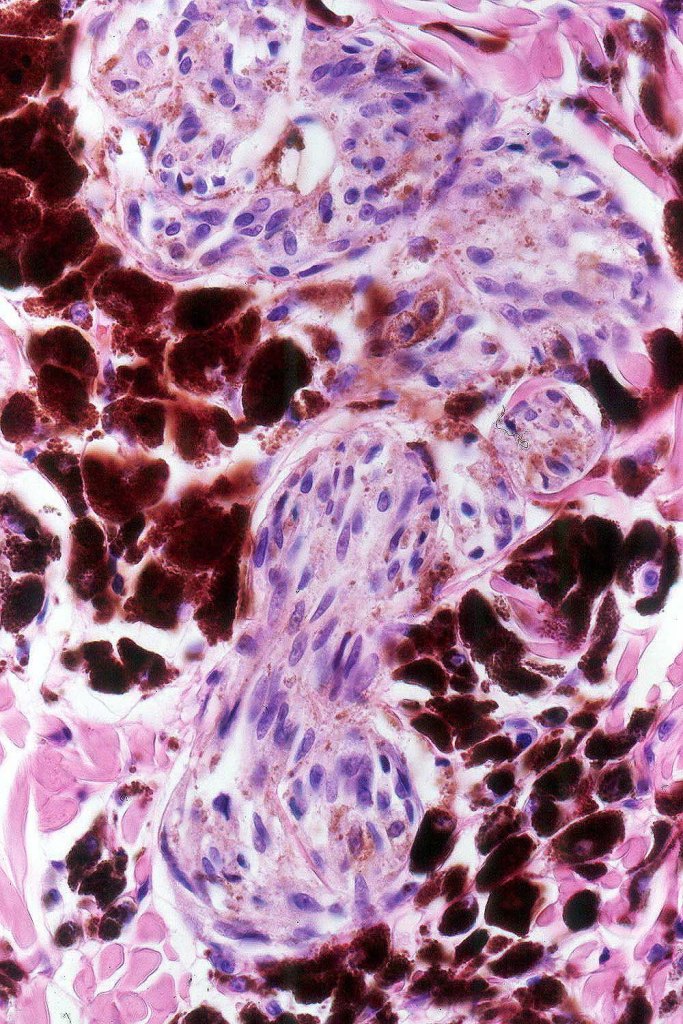

Combined Spitz & common blue nevus